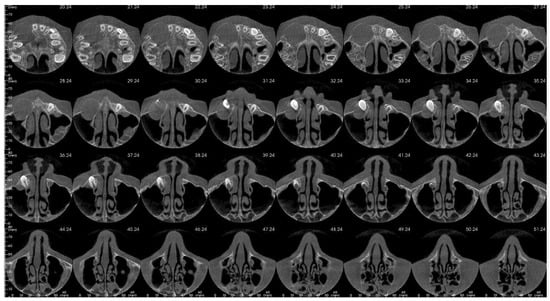

That finding necessitated further diagnostics with CBCT (Figure 4, Figure 5, Figure 6 and Figure 7). A 3D radiograph confirmed a round, well-demarcated, noninflammatory cyst-like lesion extending from Teeth 11 to 15.

Figure 4.

CBCT before treatment—sagittal view.

Figure 5.

CBCT before treatment—axial view.

A hypodense focus representing a loss of osseous tissue surrounded the crown of the displaced upper right permanent canine. The unerupted first and second premolars were dislocated and rotated, and Tooth 12 also presented mesiorotation and mesioinclination. The teeth involved in the lesion had open apices and no sign of root resorption. The alveolar bone was deformed, especially in the vestibulopalatal dimension, with a noticeable displacement of the medial interior wall of the right maxillary sinus.